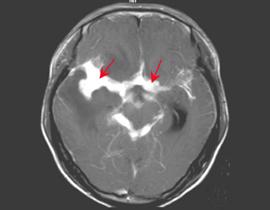

血常规检查大多正常,部分患者血沉可增高张博士医考论坛bbs.guojiayikao.com,伴有抗利尿激素异常分泌综合征的患者可出现低钠和低氯血症。约半数患者皮肤结核菌素试验阳性或胸部X线片可见活动性或陈旧性结核感染证据。CSF压力增高可达400mmH2O或以上,外观无包透明或微黄,静置后可有薄膜形成;淋巴细胞显著增多,常为(50~500)×106/l.蛋白增高,通常为1~2g/L,糖及氯化物下降,典型CSF改变可高度提示诊断。CSF抗酸染色仅少数为阳性,CSF培养出结核菌可确诊,但需大量脑脊液和数周时间。CT可显示基底池和皮质脑膜对比增强和脑积水。